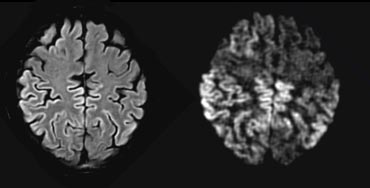

Fazekas scale for WM lesions

On MR, white matter hyperintensities (WMH) and lacunes - both of which are frequently observed in the elderly - are generally viewed as evidence of small vessel disease.

The Fazekas-scale provides an overall impression of the presence of WMH in the entire brain.

It is best scored on transverse FLAIR or T2-weighted images.

Score:

• Fazekas 0: None or a single punctate WMH lesion

• Fazekas 1: Multiple punctate lesions

• Fazekas 2: Beginning confluency of lesions (bridging)

• Fazekas 3: Large confluent lesions

The Fazekas scale for WM lesions predicts future disability in elderly. The Fazekas scale for WM lesions predicts future disability in elderly.

Fazekas 1 is considered normal in the elderly.

Fazekas 2 and 3 are pathologic, but may be seen in normally functioning individuals.

They are however, at high risk for disability.

In 600 normally functioning elderly people the Fazekas score predicted disability within one year (table). In the Fazekas 3 group 25% was disabled within one year (10).

Three year follow-up shows that severe white matter changes independently and strongly predict rapid global functional decline (17).